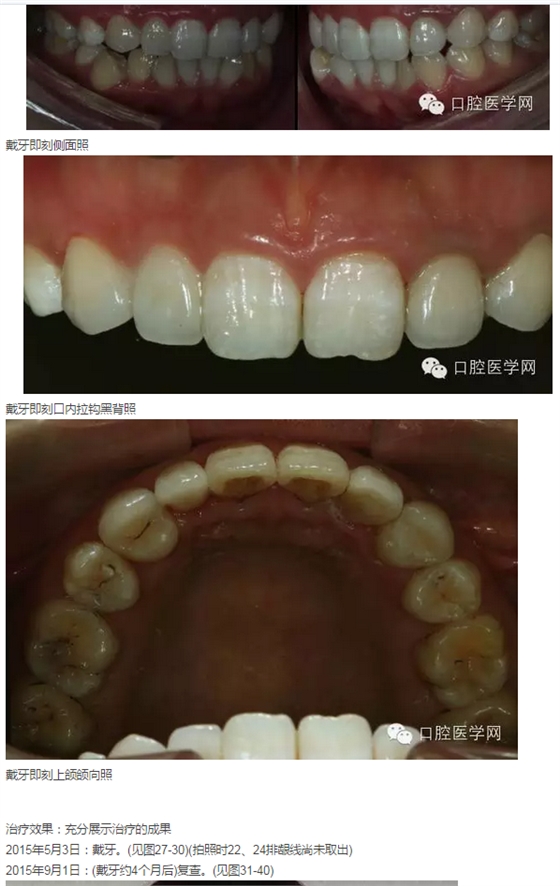

2015年4月1日:探討美學(xué)蠟形,不備牙下制作臨時(shí)飾面,試戴。

2015年4月16日:復(fù)查,調(diào)改。拍照。(見(jiàn)圖16-20)

2015年4月23日:在確定形態(tài)的臨時(shí)飾面上定深、備牙(見(jiàn)圖21-23),取模,再次制作臨時(shí)飾面。

2015年5月3日:戴牙。(見(jiàn)圖24-30)(拍照時(shí)22、24排齦線尚未取出)